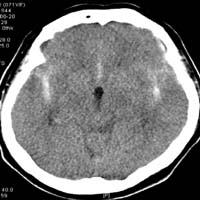

<³úÁöÁÖ¸·ÇÏÃâÇ÷>

<¼ö¼ú

Àü>

³úµ¿¸Æ·ù¿¡

ÀÇÇÑ ÁöÁÖ¸·ÇÏÃâÇ÷ÀÇ CT¼Ò°ß ¹× Ç÷°üÁ¶¿µ¼ú¿¡¼

Àü±³Å뵿¸Æ¿¡ µ¿¸Æ·ù°¡ º¸À̰í ÀÖ´Ù.

Àå¸é> <¼ö¼ú

ÈÄ>

¼ö¼ú

ÈÄ µ¿¸Æ·ù°¡ º¸ÀÌÁö ¾ÊÀ¸¸ç µ¿¸Æ·ù °æºÎ¿¡

Ŭ¸³ÀÌ µé¾î°¡ ÀÖ´Â °ÍÀÌ º¸À̰í

ÀÖ´Ù.